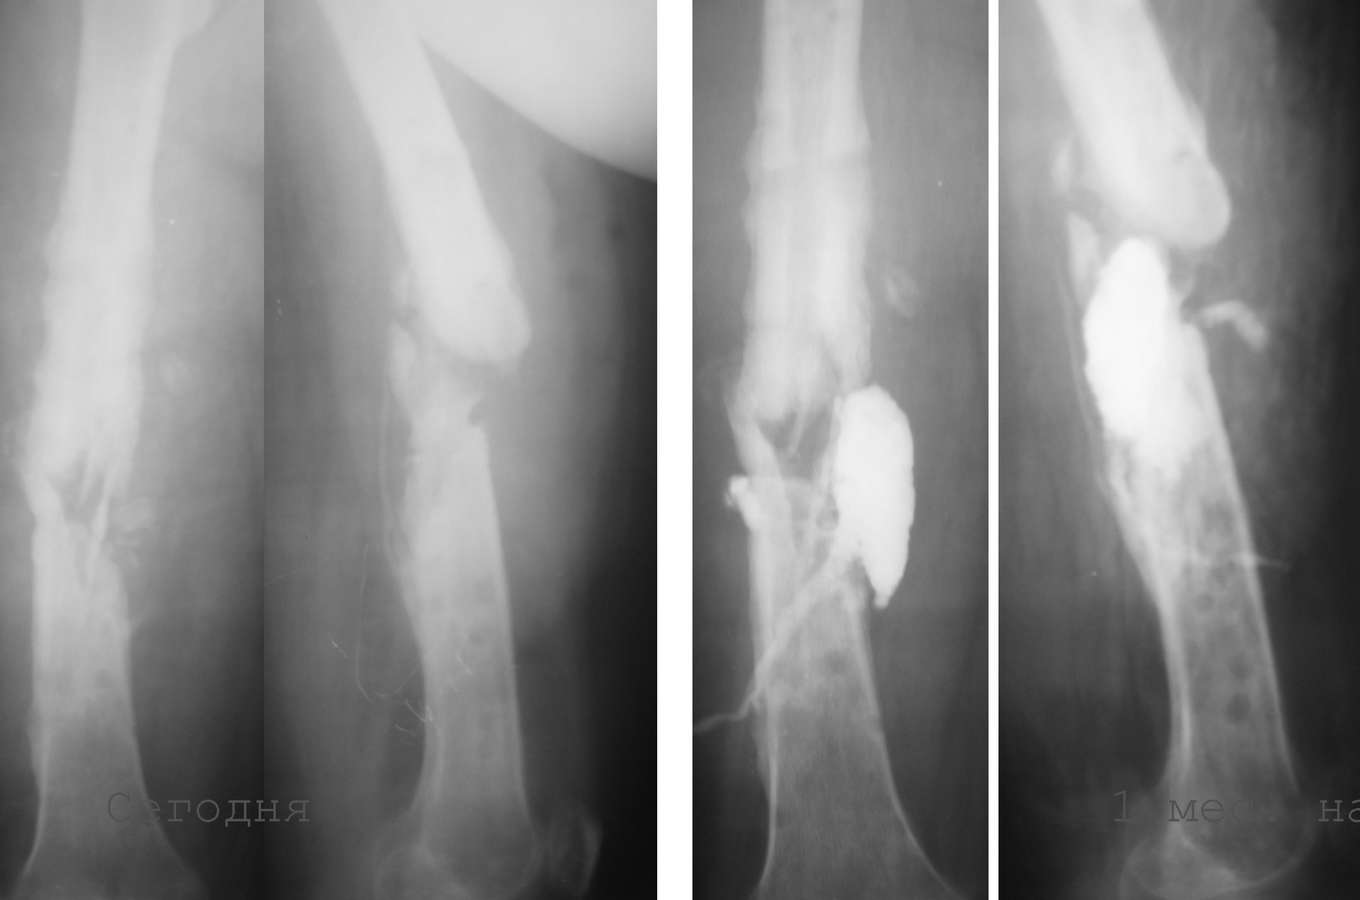

Ложный сустав бедра - мнения по татктике

Коллеги, доброго времени...Хочу выслушать мнения по тактике лечения пациентки примерно 35 лет.

1. 14 мес назад (летом 2008 г)- перелом бедра, оскольчатый, закрытый. Интрамедуллярныйостеосинтез гвоздем Кюнчера, несостоятельная фиксация, поэтому дополнили кокситом.

2. Через 4 мес. ввиду отсутствия перспектив сращения - я выполнил остеосинтез аппаратом Илизарова. В отдельные периоды была надежда наконсолидацию. В аппарате 6-7 мес, постоянные выделения в области стержня - сняли аппарат.

3. 2 мес. ходит с лонгетой, имеется патологическая подвижность. В течение месяца после снятия сохранялись выделения из отверстия, где был стержень, температура до 38, иногда отсутствовала. Сделал фистулу с уверенностью, что это стержневой остеомиелит.

Но контраст ушел в зону перелома, и эвакуировал около 20 мл лизированной крови (без гноя).

Температура исчезла, свищ практически закрылся.

4. Сейчас два раза в неделю промываем эту полость, всегда - около 7 мл сукровицы. Иногда - Субфебрильная температура.